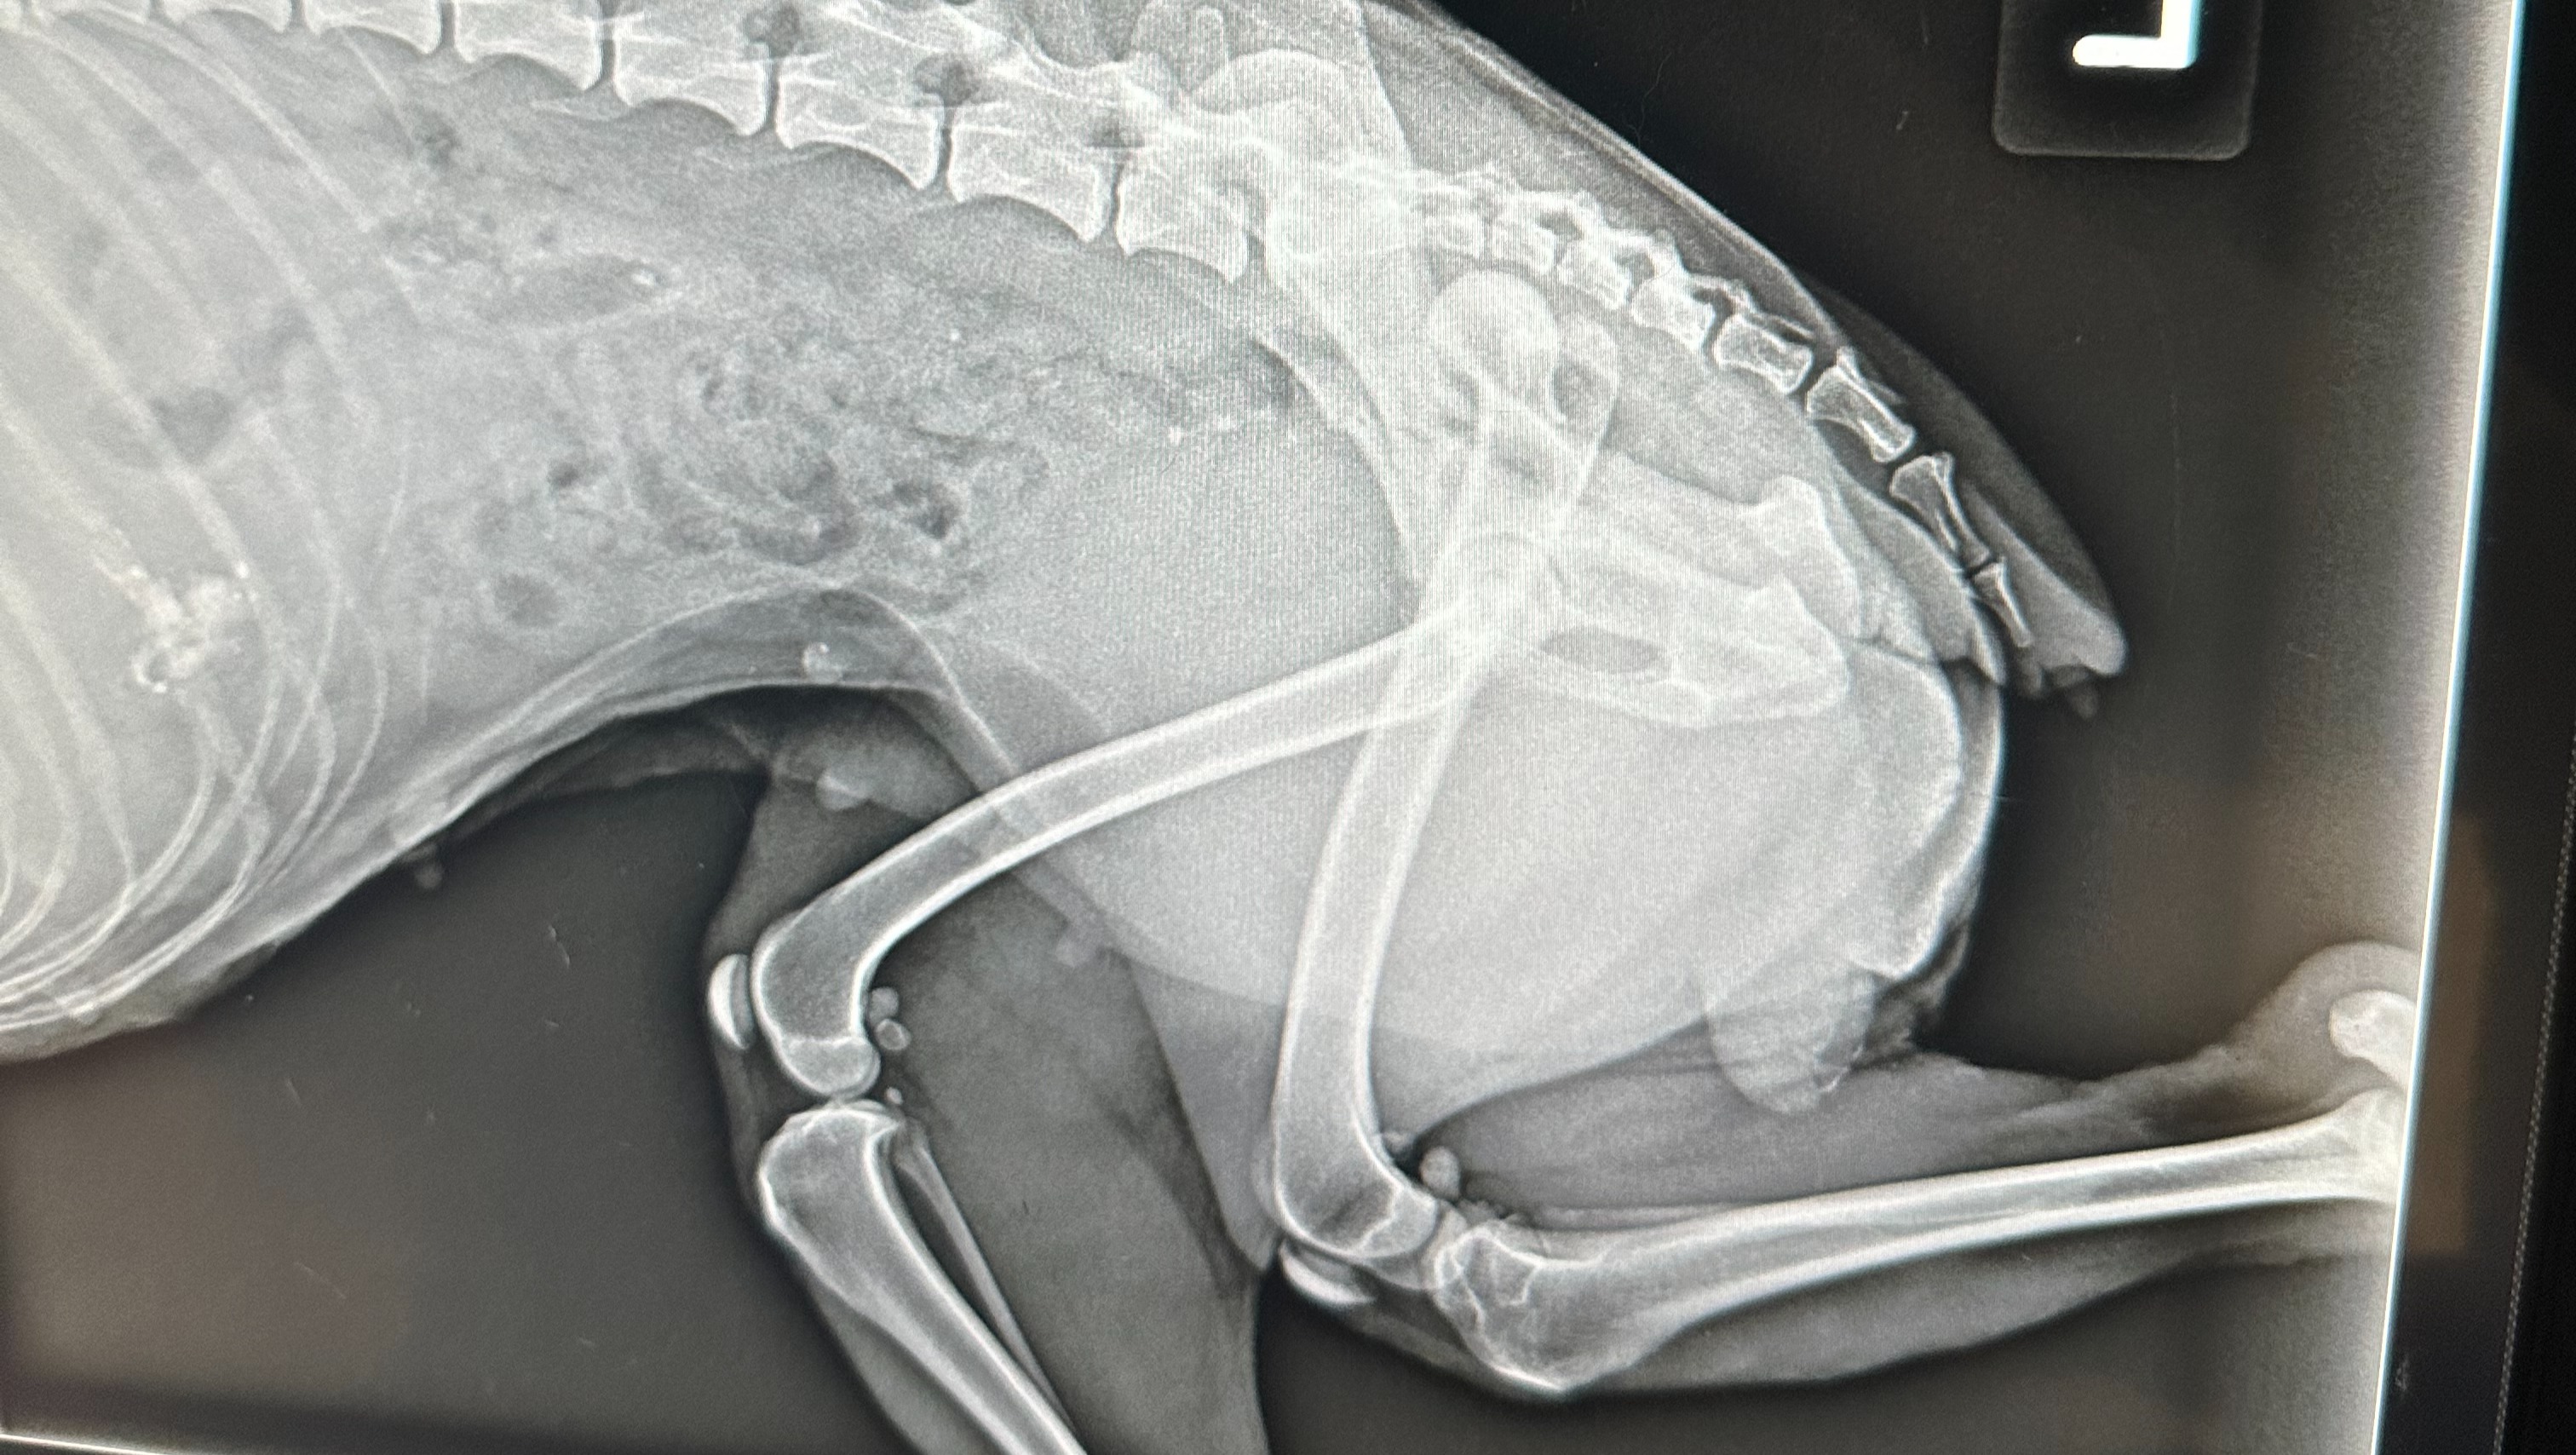

"Autumn" as we have decided to call her is in the current care of a vet and the initial cost to be seen was $510.23. The vet discovered that Autumn has a spinal fracture and a dislocated hip, that would require surgery to have the head of the femur removed. He states that this would heal quite well in a dog this size as she is a smaller dog. This surgery is estimated to cost between $1,136.60 - $1,407.17. She also needs IV fluids overnight as she is dehydrated, pain medication, and antibiotics for her wounds.